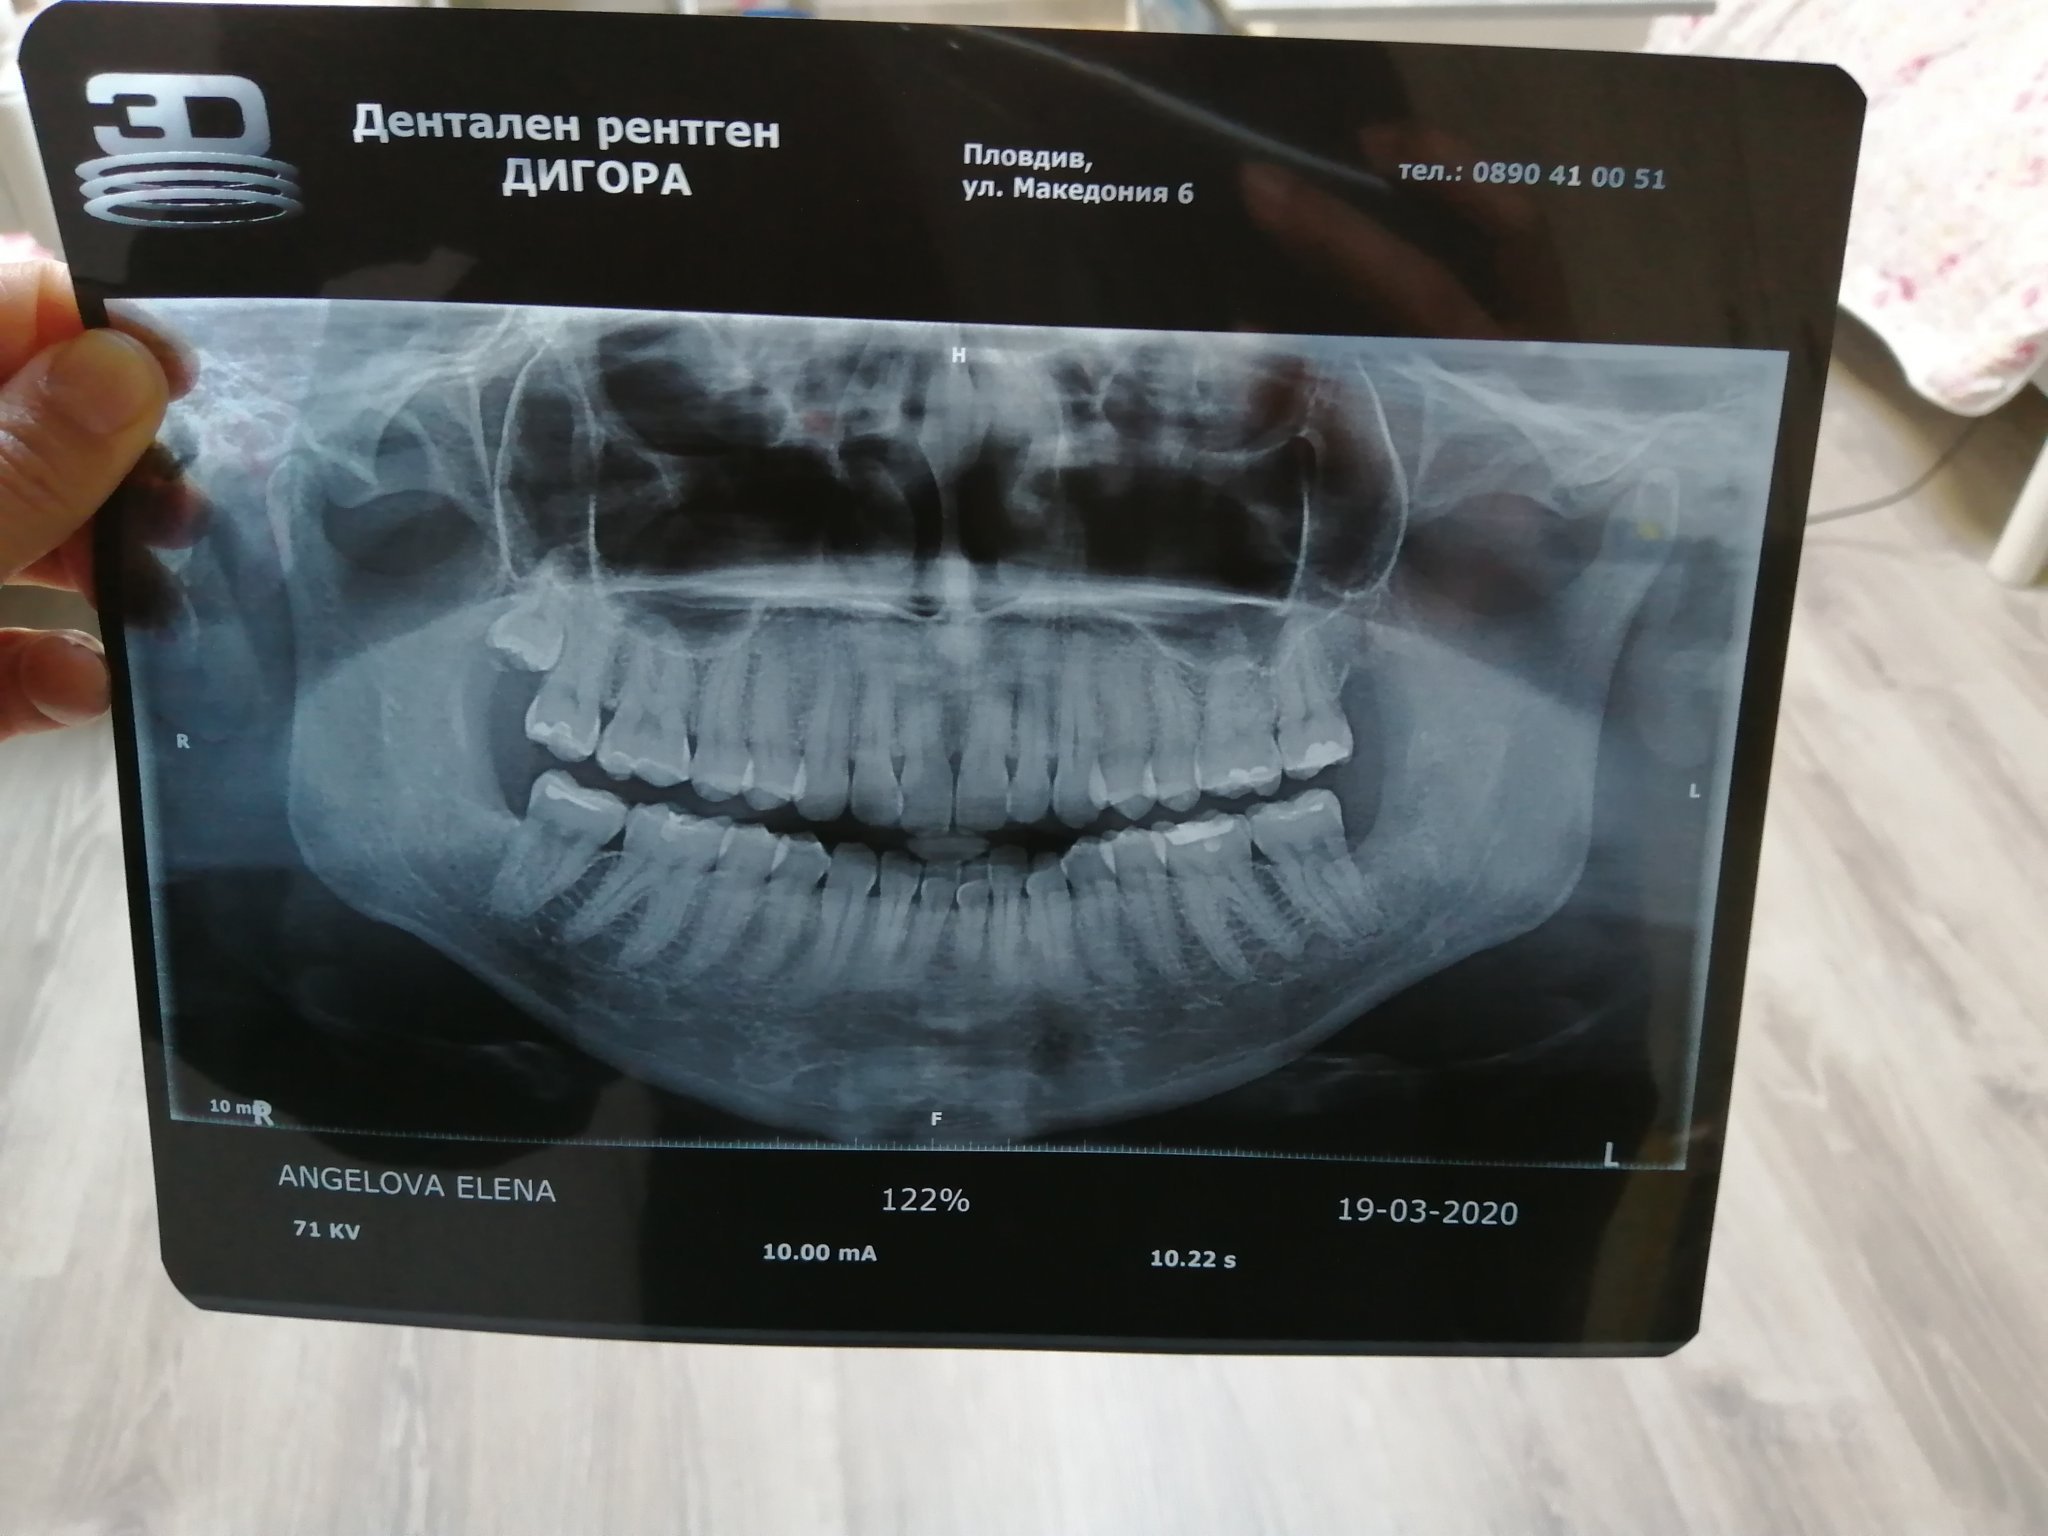

Здравейте.Искам да попитам зъболекарите във форума.Преди около 7 месеца си извадих трите мъдреца,но долният ляв ми създаваше проблеми.Отидох при друг хирург и се оказа ,че имам абцес почистиха го,но оттам нататък пак не се чувствам добре минаха вече 4 месеца.След това правих консултация още с 3 хирурга в Пловдив и всеки казва че е зарастнало и е добре'но аз не се чувствам добре.Последният ми назначи физиотерапия и сега ходя защото имам прещтракване на челюстта,но много ме е страх пак да нямам абцес.Прилагам и снимка благодаря предварително за отговора ,